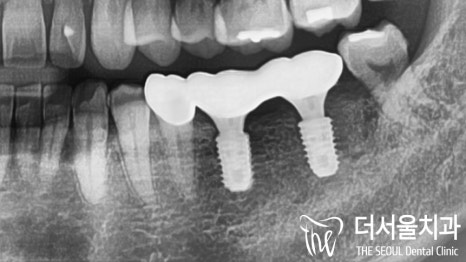

계획했던대로 성남치과추천

모든 과정을 마쳤습니다.

텅 비어있던 곳이 튼튼한 임플란트로

메꿔져 있는 것을 볼 수 있는데요.